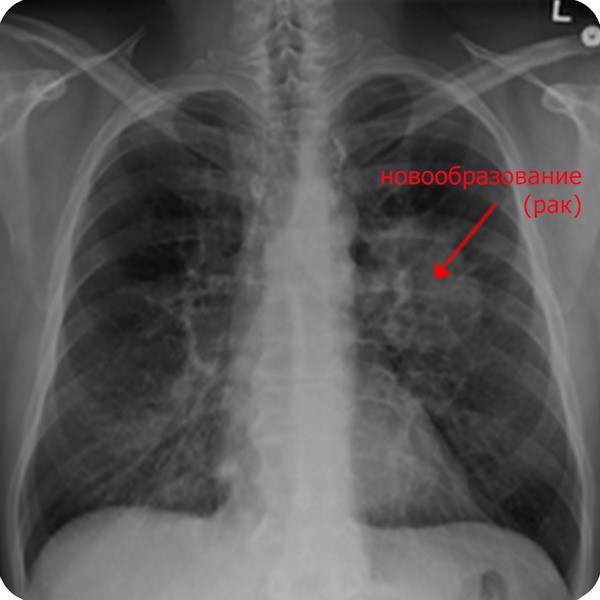

Но мы помним, что радон — газ. Кроме того, продукт его распада, хоть и не газ, но рождается в воздухе, в одноатомном виде. Как и последующие нуклиды, будет очень мелкой пылью. Газ и пыль могут попасть в части организма, где нет защитного слоя — дыхательные пути и легкие. В них реализуется весь 20-и кратный вред от альфа-лучей плюс часть от беты и гаммы.

Согласно отчету всемирной организации здравоохранения загрязнение воздуха помещений радоном является причиной возникновения рака легких в районе от 3 до 14% случаев, что занимает второе место по частоте после курения [5][6].

Учитывая, что ежегодно от рака легких умирает 1,5 миллиона человек, среди них 150 тысяч случаев вызваны именно радоном. Таким образом, среди некурящих радон по канцерогенности выходит на первое место. Человек, дышащий загазованным воздухом около фабрики или проспекта с меньшей вероятностью заболеет раком легких, чем человек дышащий только свежим воздухом, но проживающий или работающий в помещениях, где земля или строительные материалы неприметно выделяют радиоактивный газ без цвета и запаха.